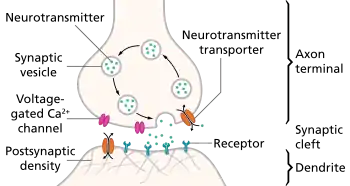

Psychoactive drugs operate by temporarily affecting a person's neurochemistry, which in turn causes changes in a person's mood, cognition, perception and behavior. There are many ways in which psychoactive drugs can affect the brain. Each drug has a specific action on one or more neurotransmitter or neuroreceptor in the brain.

Drugs that increase activity in particular neurotransmitter systems are called agonists. They act by increasing the synthesis of one or more neurotransmitters, by reducing its reuptake from the synapses, or by mimicking the action by binding directly to the postsynaptic receptor. Drugs that reduce neurotransmitter activity are called antagonists, and operate by interfering with synthesis or blocking postsynaptic receptors so that neurotransmitters cannot bind to them.[51]

Exposure to a psychoactive substance can cause changes in the structure and functioning of neurons, as the nervous system tries to re-establish the homeostasis disrupted by the presence of the drug (see also, neuroplasticity). Exposure to antagonists for a particular neurotransmitter can increase the number of receptors for that neurotransmitter or the receptors themselves may become more responsive to neurotransmitters; this is called sensitization. Conversely, overstimulation of receptors for a particular neurotransmitter may cause a decrease in both number and sensitivity of these receptors, a process called desensitization or tolerance. Sensitization and desensitization are more likely to occur with long-term exposure, although they may occur after only a single exposure. These processes are thought to play a role in drug dependence and addiction.[52] Physical dependence on antidepressants or anxiolytics may result in worse depression or anxiety, respectively, as withdrawal symptoms. Unfortunately, because clinical depression (also called major depressive disorder) is often referred to simply as depression, antidepressants are often requested by and prescribed for patients who are depressed, but not clinically depressed.